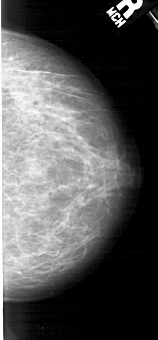

A_1982_1.LEFT_MLO

LEFT_MLO LINES 5296 PIXELS_PER_LINE 2596 BITS_PER_PIXEL 12 RESOLUTION 43.5 OVERLAY